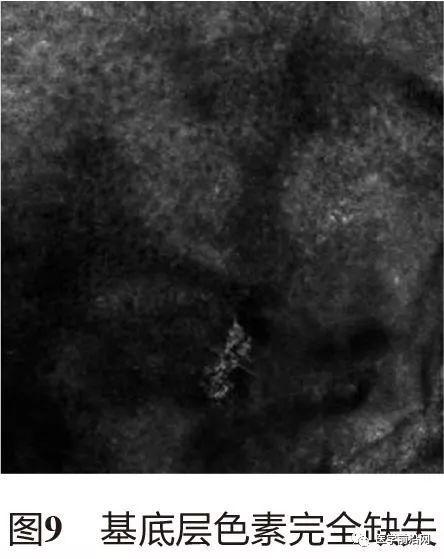

2.1 白癜风 白癜风具有特征性的RCM表现,与周围正常皮肤比较,白斑区域基底层明亮的(高折光)色素环缺失或不完整(图2)。稳定期时,白斑区基底层色素完全缺失,白斑区与正常皮肤界限清晰(图3,图4);进展期时,白斑区与周围正常交界处皮肤基底层色素完全或部分缺失,正常皮肤与白斑区界限模糊,交界区域真皮乳头可见高折光色素颗粒或中度折光的单一核细胞浸润(图5,图6);治疗后,肉眼可见新生色素岛之前,镜下可见白斑区毛囊周围黑素细胞呈树枝状增殖或皮损周围正常皮肤黑素细胞呈树突状增殖活跃(图7,图8),随后,白斑区色素逐渐增多,RCM下可动态观察到色素的恢复(图9~图11)。